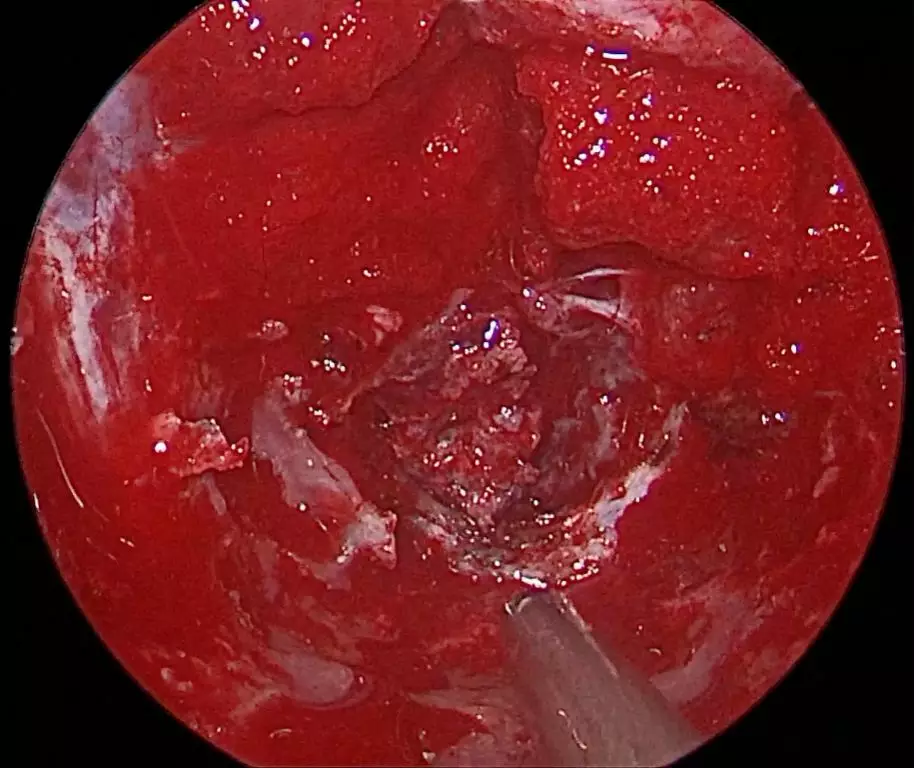

• Debulking Tumor

• After debulking, dissecting tumor margin

• Tumor embedding brainstem appeared

• Tumor in CPA, with 30° angle rigid

• After tumor removal,brainstem